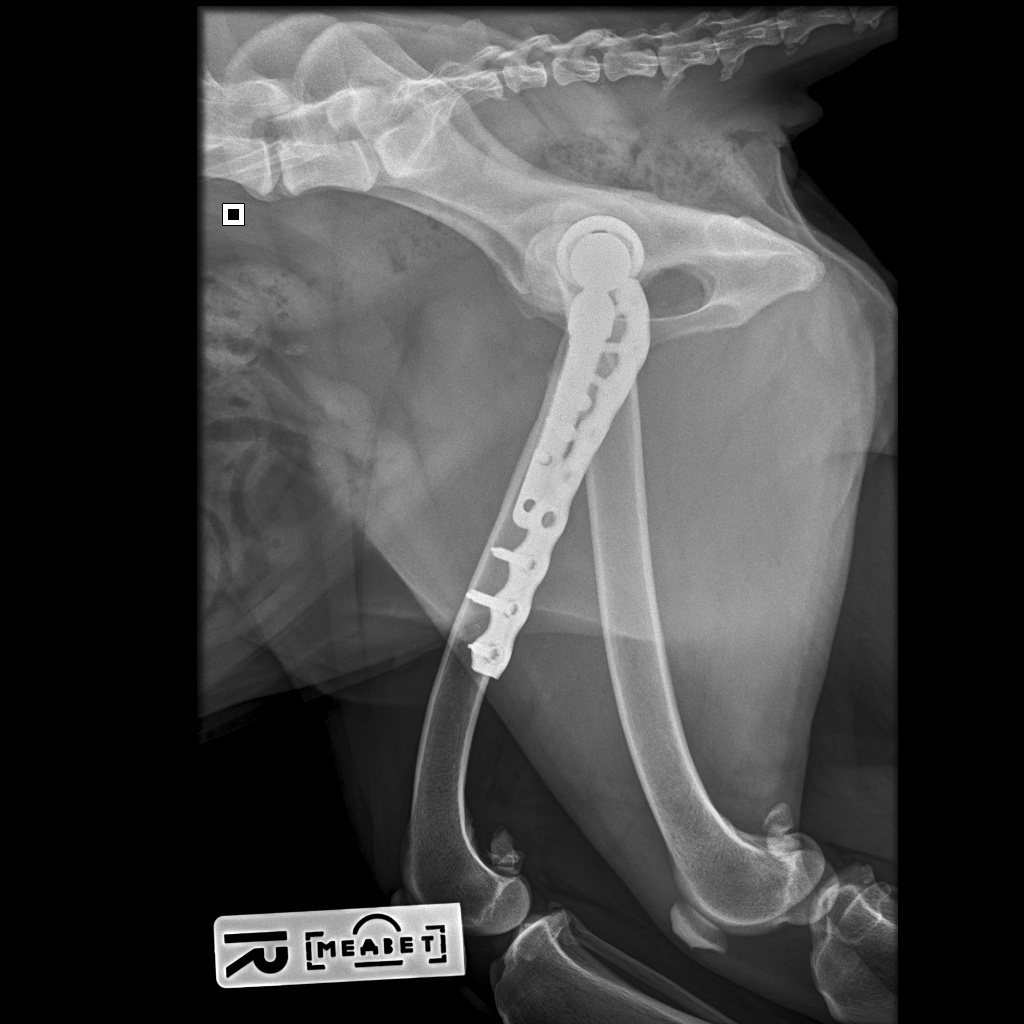

18.08.2025 мы съездили на контрольный рентген. Можно было сделать рентген и в любой ближайшей клинике, но мы предпочли не рисковать. Во-первых, делать снимки нужно было в каких-то особенных проекциях, на которых виден процесс приживления, а, во-вторых, для такого рентгена требовался наркоз. Потому мы решили не искать легких путей и сразу сделать там, где гарантированно все получится в лучшем виде. Так что записались мы в Медвет в Троицке и покатили к 9 утра.

Далее стандартная процедура: разговор с доктором о самочувствии собаки и наличии жалоб, осмотр анестезиологом и Басю забрали. Где-то через час нам вернули ее уже полностью отошедшую от наркоза, сказали, что все у нас хорошо, ограничения с нас сняты и мы можем быть свободны.

Вот как теперь выглядит ее внутренний мир